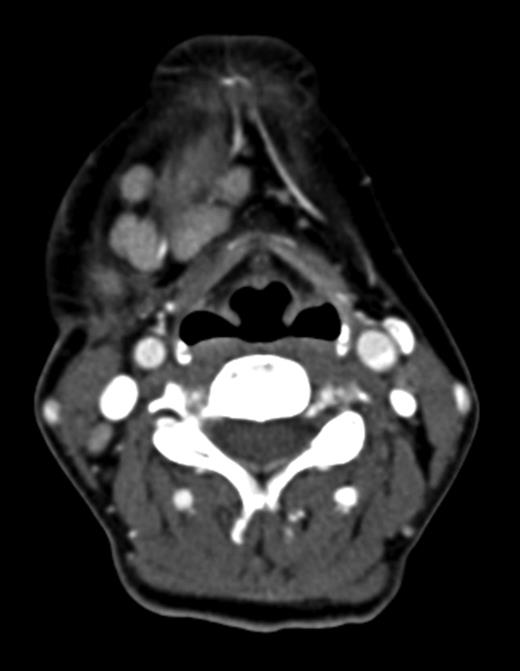

Computed tomography (CT) identified several enlarged submandibular lymph nodes (Figs 1 and 2).

Axial CT neck (post contrast) showing enlarged right submandibular nodes.